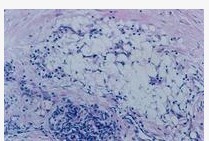

組織病理:黃瘤病是反應腫瘤,不同型別黃瘤顯微結構相近,無需鑑別診斷。主要表現為黃瘤外周血管周圍出現淋巴細胞和組織樣細胞,這些細胞含有脂質。在切片固定過程中,脂質發生溶解,細胞質呈現泡沫現象。泡沫細胞即充滿吞噬脂質的巨噬細胞,為黃瘤的主要成分。另外,還有具有特徵性的多棱成環狀排列的巨細胞即Touton細胞。被吞噬脂質的超微結構包括含脂蛋白、雙折射膽固醇晶體和磷脂的空泡,且磷脂呈現胞內髓鞘質圖像;另外還存有脂肪酸和中性脂肪。其他一些特徵包括發疹型黃瘤呈一致性炎症現象和時間較長的黃瘤呈現纖維化增加的成纖維細胞反應。需要注意的是在組織中見到泡沫細胞或脂質時,需排除麻風、深部真菌病、組織細胞瘤及類脂質漸進性壞死等。